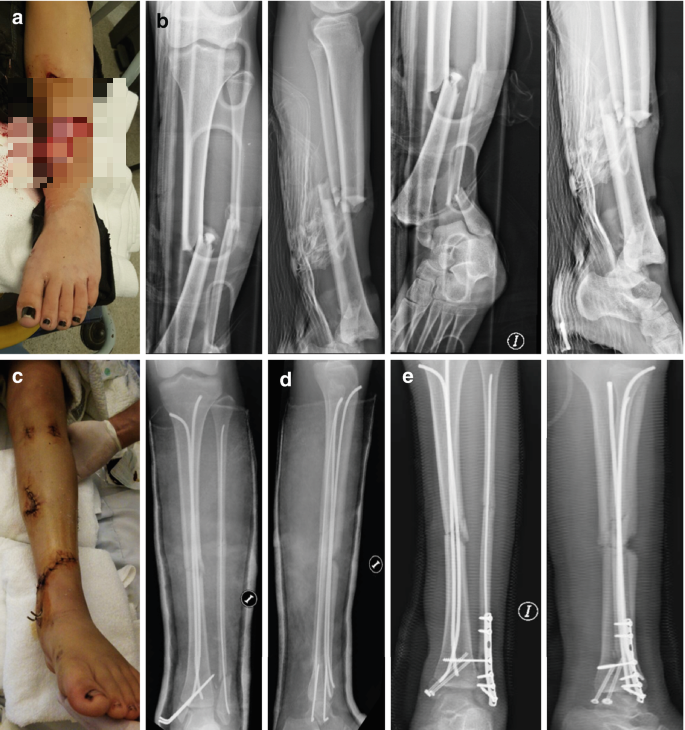

개방성골절의 정의와 위험성

개방성골절은 골절 부위가 피부를 뚫고 외부로 노출된 상태를 의미합니다. 이는 단순 골절과는 달리 감염 위험이 매우 높은 응급 상황으로 분류됩니다.

개방성골절의 특징은 다음과 같습니다.

- 뼈가 피부 밖으로 노출

- 외부 세균 감염 위험 높음

- 출혈이 심할 수 있음

- 주변 조직 손상 동반

치료는 매우 긴급하고 복합적으로 이루어집니다.

- 응급 세척 및 소독

- 항생제 투여

- 수술적 고정

- 연부조직 복원

개방성골절은 단순히 뼈 문제를 넘어서 "감염 관리"가 치료의 핵심이 되는 골절입니다.